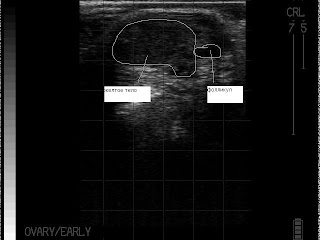

Определение стельности.

Обосновано применение ультразвука в качестве диагностики стельности с 30-ого дня. Почему нельзя раньше? Ошибочно читать, что просто не увидишь плода. Плод виден и на 25-й день. Есть две причины почему не рекомендуют раньше. Первая – это возможный натуральный аборт (на сроке 25-30 дней – максимальная предрасположенность к этому) и специалист ошибочно ведет корову к отелу как стельную. Требуется перепроверка. Конечно, перепроверять необходимо и при исследовании на более поздних сроках, но вероятность аборта выше на раннем сроке (до 30 дней). Вторая причина – это инструментальный аборт. Вероятность его минимальна, но все же существует. Дело в том, что прикрепление эмбриона к стенке матки происходит на 25-28 день. И манипуляции с маткой (особенно без опыта и осторожности) чреваты абортом. Подчеркну, что не ультразвук вызывает аборт (разумеется при нормальной интенсивности, частоте луча), а именно манипуляции.

В зависимости от размера эмбриона можно определить его примерный возраст:

28 дней:

30 дней – 1 см

35 дней – 1,5 см

40 дней:

40 дней – 2,0 см

45 дней – 2,5 см.